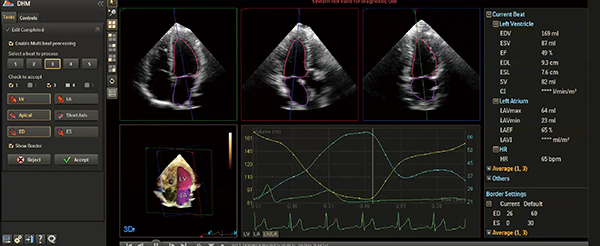

1.HeartModelA.I.

フィリップスでは,解剖学的知識であるAnatomical Intelligence(以下,A.I.)を使用したソフトウエアの開発を行い,超音波診断装置に搭載している。初めてリリースされたA.I.搭載解析ソフトウエアは,2015年に販売開始した“HeartModelA.I.”である(図1)。HeartModelA.I.では,さまざまな心臓の形状や大きさを含んだ約1000例以上の3Dエコー画像をデータベース化し,ナレッジベースに基づき左室と左房の容積を算出する。従来のシンプソン法を用いた2Dでの計測と比較して,1ボタンのシンプル操作で高精度な定量評価が可能となり,検者の習熟度に依存しない,短時間での心機能評価を可能にした。

図1 HeartModelA.I.

左室・左房の容積や1心周期における容積変化を1ボタンで算出することが可能